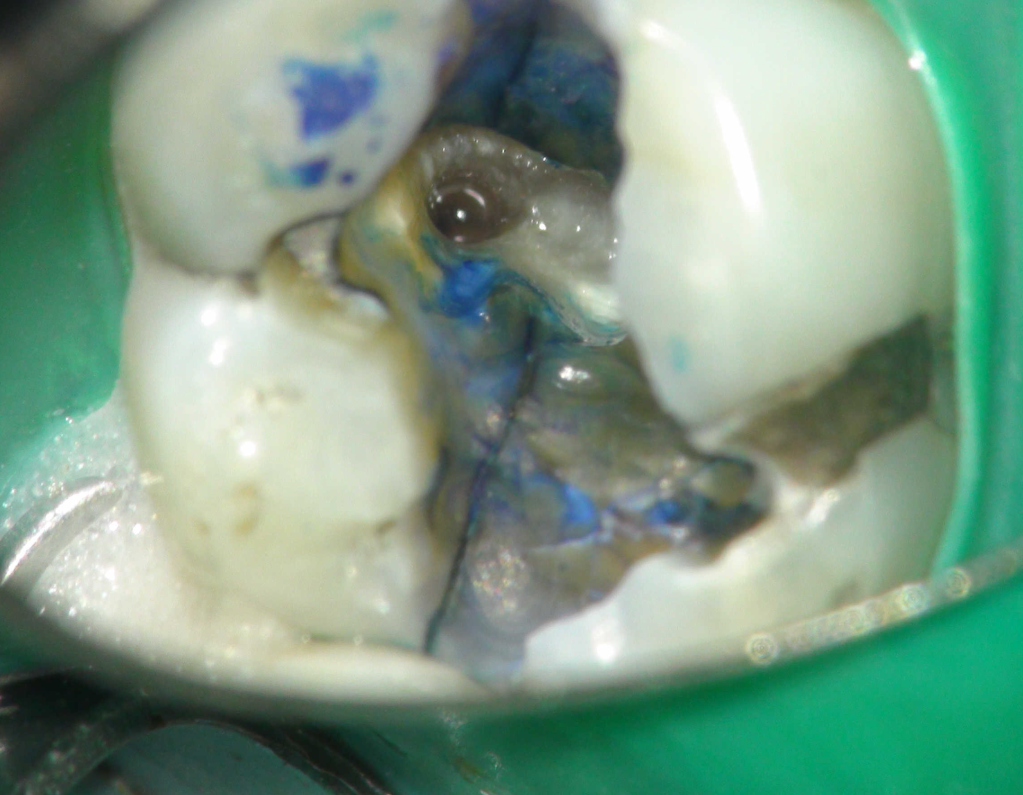

Reconstrucción preendodóntica

Reco pared vesticular

Reco preendo + 4 conductos molar superior

Reco preendo, 2o Molar superior